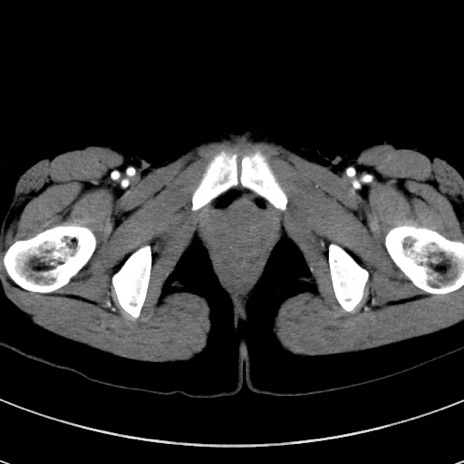

症例17(横断像)

【症例】20歳代女性

【主訴】嘔吐、下腹部痛

【現病歴】昨日夕食後に嘔吐し下腹部痛が出現。本日になっても嘔吐持続し改善しないため来院。

【身体所見】意識清明、BT 37.2℃、BP 108/67mmHg、腹部:平坦、やや硬、下腹部正中から右にかけて圧痛あり、反跳痛軽度あり、tapping pain(+)。

【データ】WBC 13600、CRP 14.94